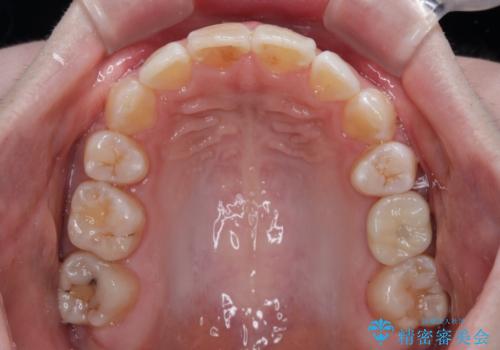

- 奥歯の欠損と、抜歯矯正の後戻りを気にして来院された患者様です。

上下前歯をワイヤー保定していましたが、強い舌の突出癖により上下ともにスペースができ、上下前歯は非接触になっていました。

舌の突出癖を改善したことで、突出感のあった口元の印象も、やや引っ込めることができました。